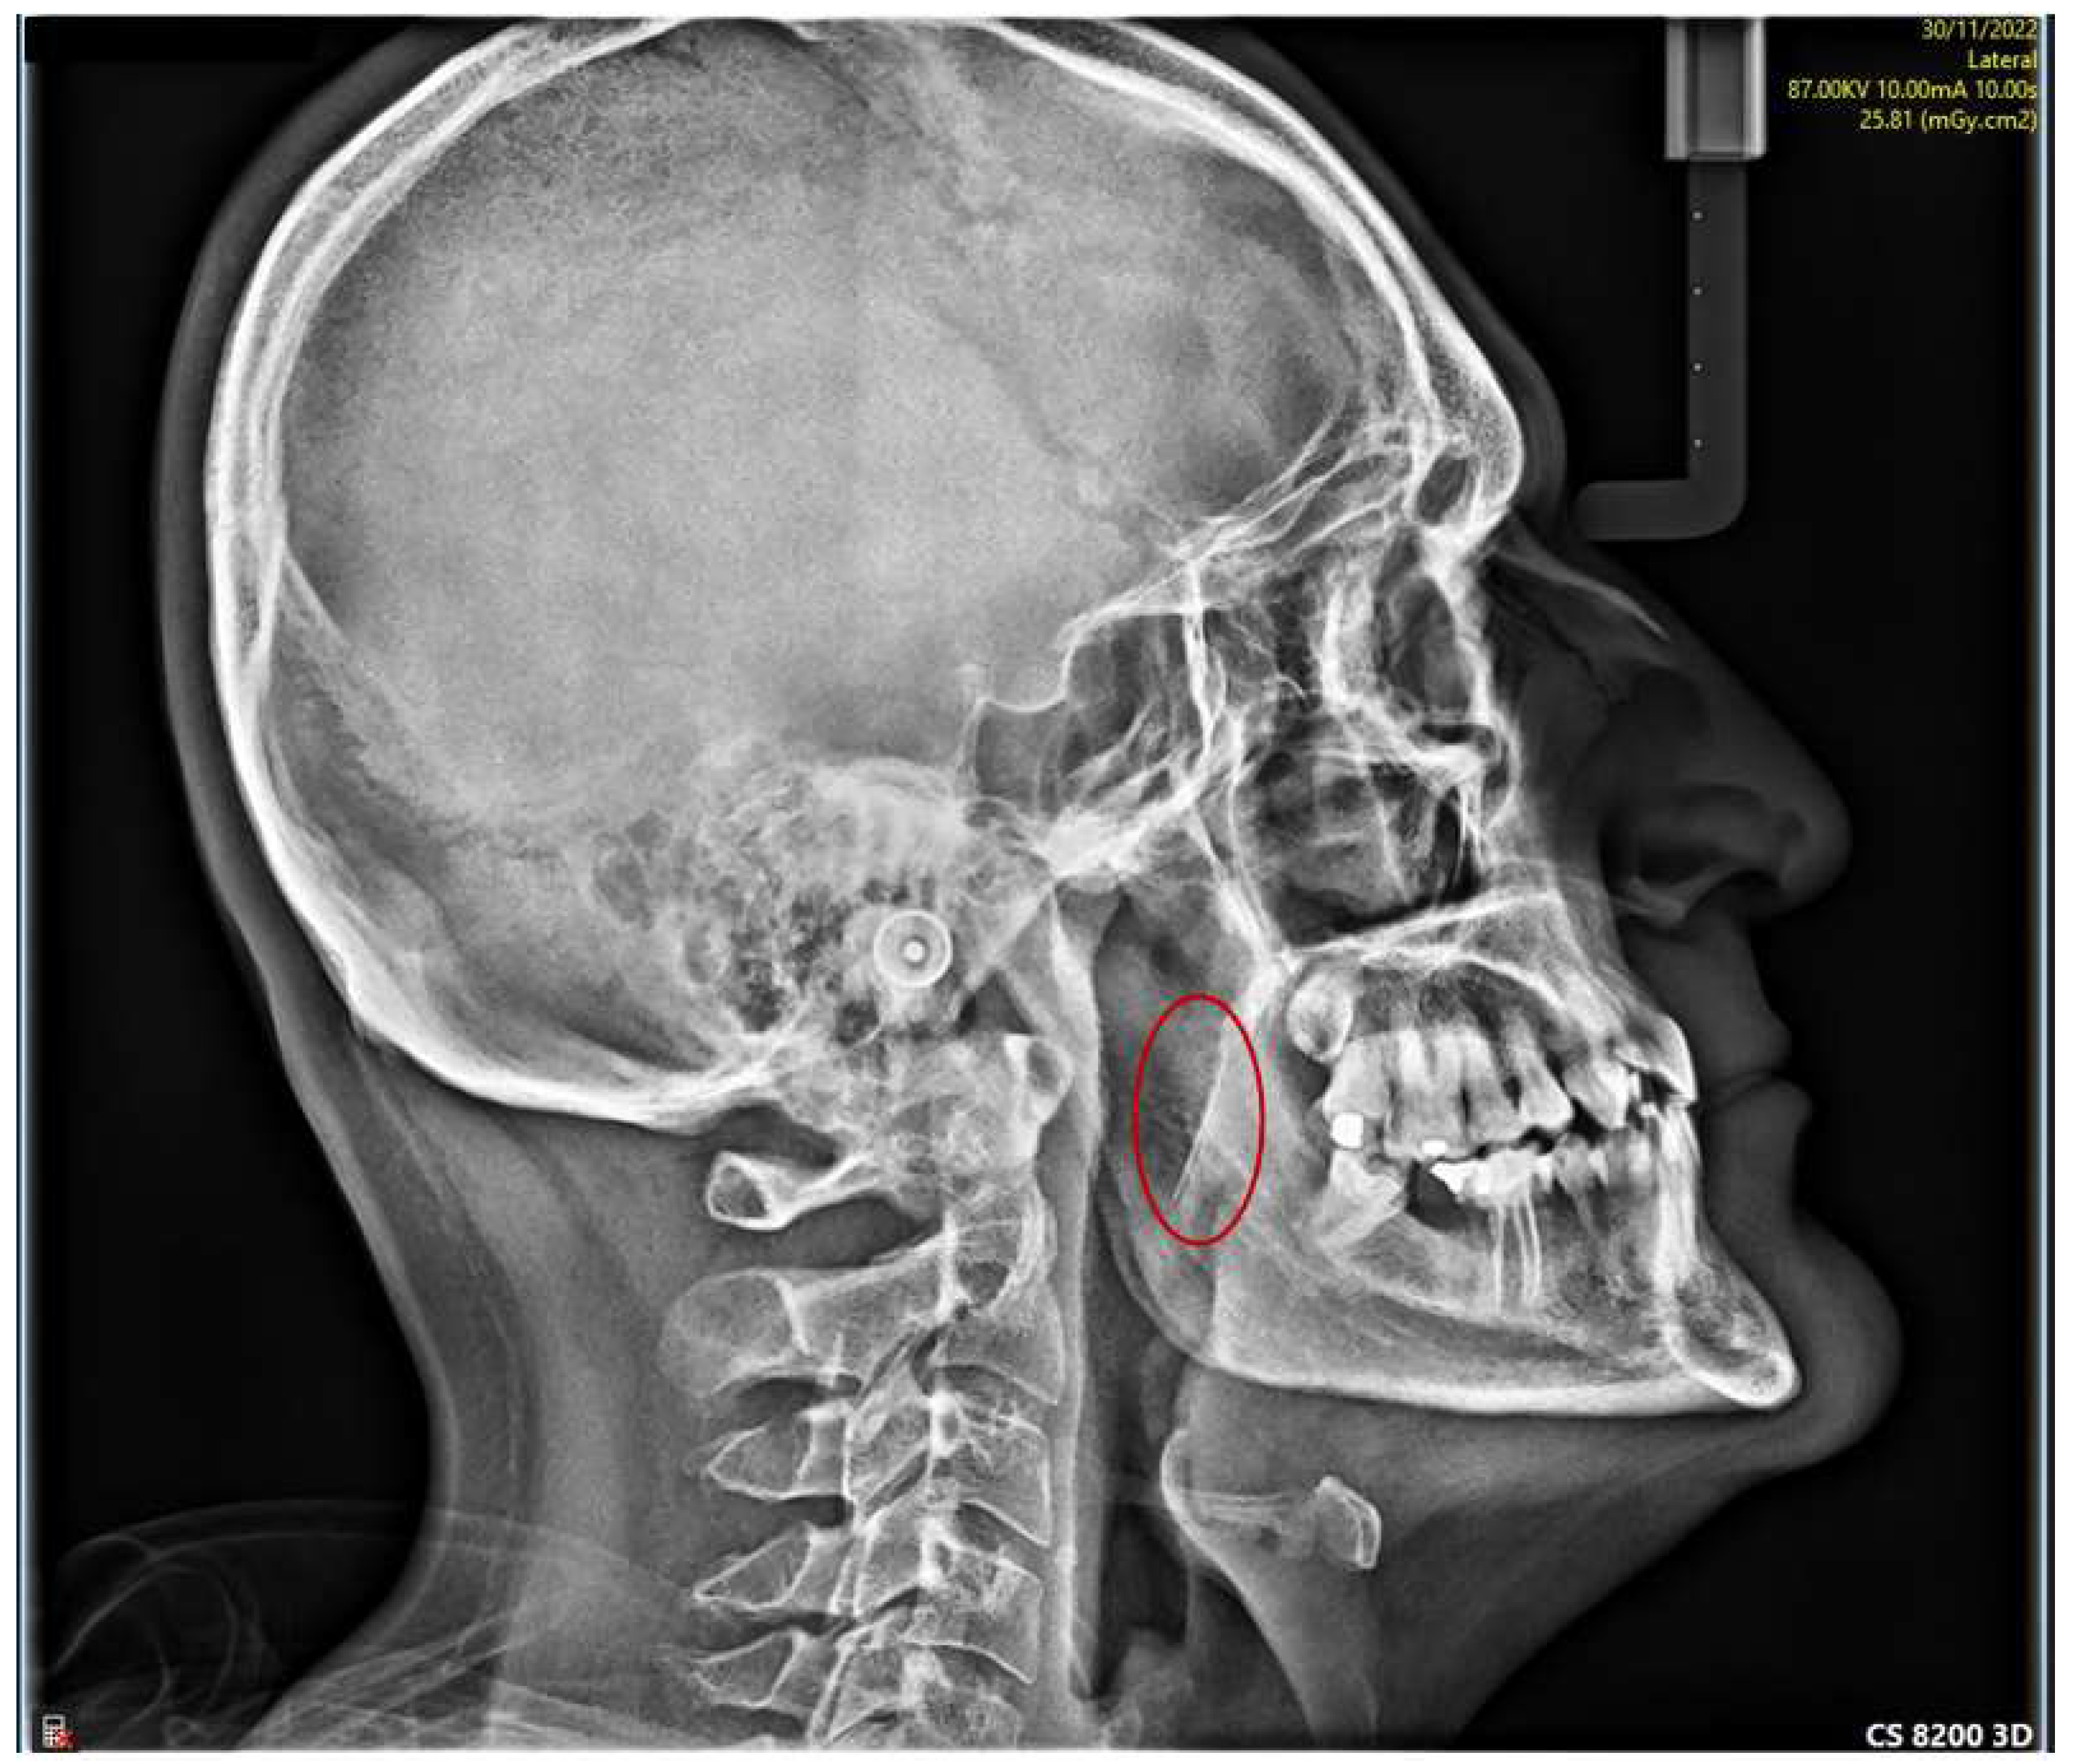

Preoperative radiographic images showing the broken needle in (A Needle Breakage In Dentistry Needle fracture during the delivery of local anaesthesia is a rare complication in modern clinical dentistry and to some extent has become a historical issue. But although rare, dental needle breakage can, and does, occur. The retrieval of a broken dental needle demands a detailed knowledge of the relevant anatomy and the application of a meticulous surgical technique. A broken. Needle Breakage In Dentistry.

Preoperative radiographic images showing the broken needle and Needle Breakage In Dentistry We report a case of. But although rare, dental needle breakage can, and does, occur. The retrieval of a broken dental needle demands a detailed knowledge of the relevant anatomy and the application of a meticulous surgical technique. Should a needle break, the practitioner must note how it. These factors are emphasized in the following article. Review of the literature. Needle Breakage In Dentistry.